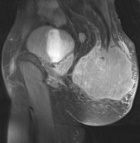

25 y/o male with chronic coccygeal pain who presents with progressive left buttock mass. Mild constipation. No other complaints. Smoker, otherwise healthy.

PE: Large, nontender mass involving L>R buttock with induration and erythema. Neurovascularly intact

Zoom image: Radiological image Radiological image.